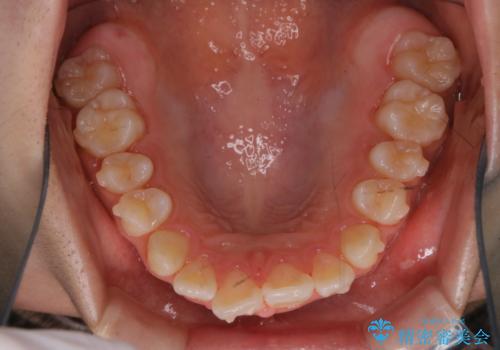

- インビザラインにて矯正治療中の方です。矯正治療の経過チェック時に歯磨き指導とクリーニングも希望とのことでした。

PMTC30分コースを行いました。